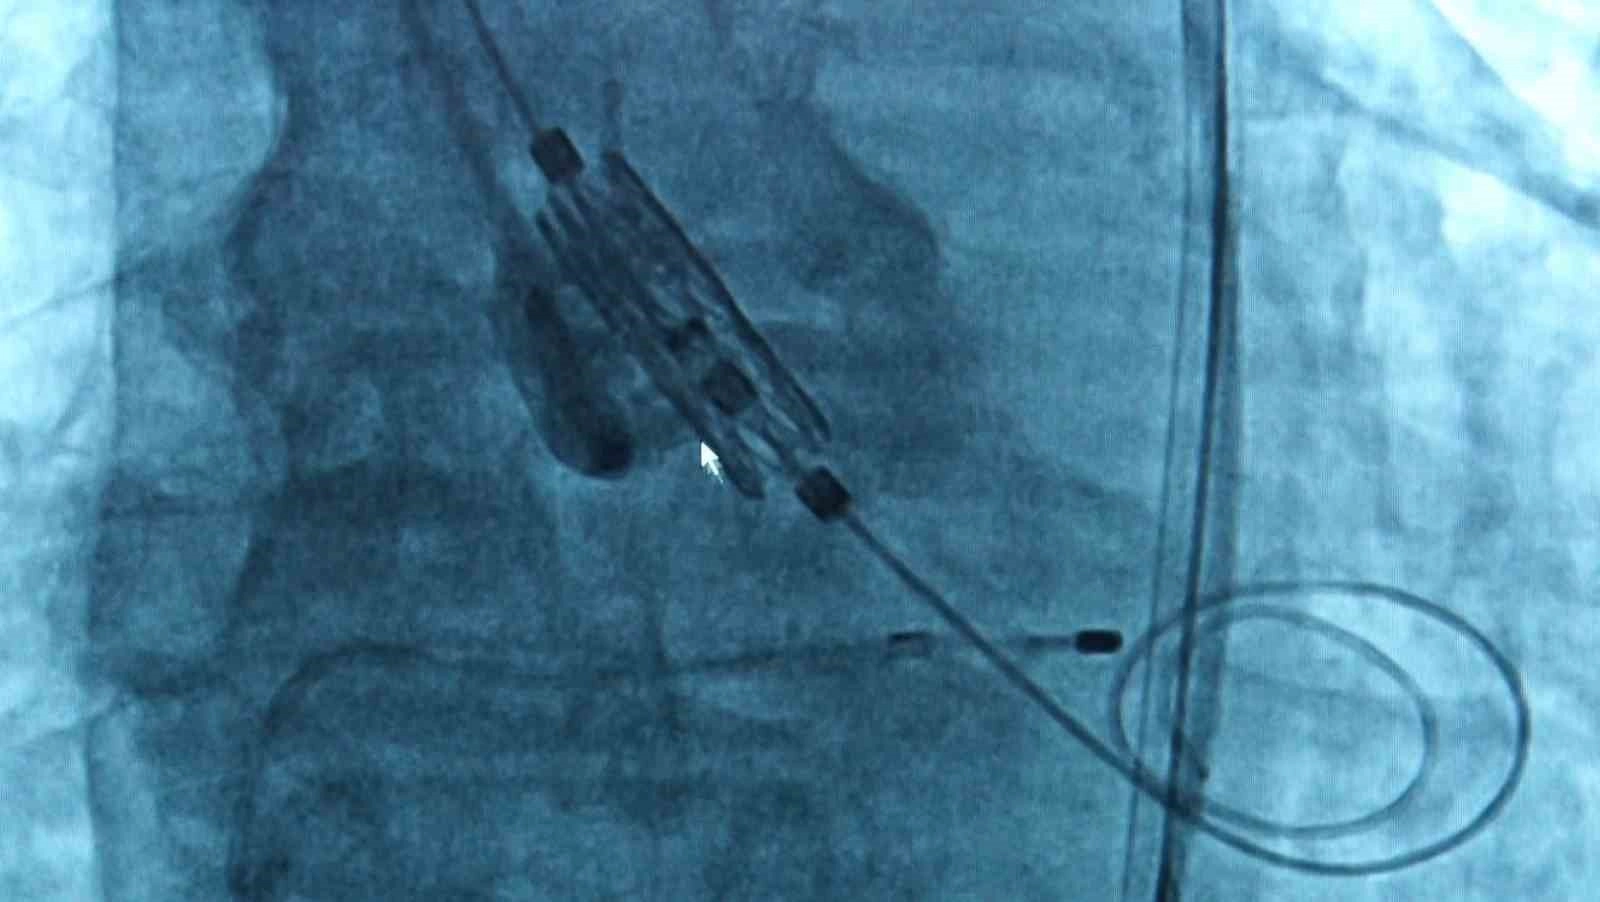

TAVI yöntemine ilişkin bilgi veren Doç. Dr. Dilay Karabulut, "Aort kapak, kalpten çıkan ana damar dediğimiz aortun ağzındaki kapak. Yaşla beraber kapakta gelişen kireçlenme ve kalsifikasyon((Vücut dokusunda kalsiyum birikmesi)a bağlı olarak kapaklar birbirine yapışmakta ve kapak alanı daralmaktadır. Bunun sonucunda kalp yeteri kadar kanı vücuda pompalayamadığı için hastada birtakım semptomlar gelişmekte, bu ilerleyerek kalp yetmezliğine kadar gitmekte. Kapak daraldığı zaman 2 tane tedavi yöntemimiz var; kapağın cerrahi olarak çıkarılması ya da TAVI dediğimiz yani kasıktan küçük bir kesi yapılarak kapağı yerleştirdiğimiz bir işlem. Eskiden daha çok cerrahi işlemler ön plandaydı. Ne yapıyorduk; hastanın göğüs kafesi açılıyor, kalbi durduruluyor, kapak yerinden çıkarılıyor ve yapay bir kapak takılıyordu. Şu an hala bazı seçilmiş hastalarda cerrahi aort kapak replasmanı yapılıyor ancak TAVI işlemi 20 yıldır tüm dünyada, ülkemizde de aynı şekilde yapılan bir işlem. Hasta için daha konforlu özellikle seçilmiş hasta gruplarında hastaneye yatış süresi daha kısa, hastanın göğüs kafesi açılmadan, kalbi durdurulmadan ve hastanede işlem sonrası yaklaşık 1 gün kadar kalıp hastayı taburcu ediyoruz. Nasıl yapıyoruz; kasıktan küçük bir kesi açıyoruz, bu kesiden bir telle kalbin içine doğru ilerliyoruz. Aort kapağın olduğu yere yeni yapay kapağı yerleştiriyoruz. Operasyon yaklaşık 1 saat kadar sürüyor. Yapılan çalışmalarla gösterildi ki artık orta risk hatta son zamanlarda düşük riskli olan grupta da TAVI işlemini yapabiliyoruz. Yapay kapaklar olduğu için tabi ki ilerleyen dönemlerde dejenerasyona uğrayabiliyor ama 10-15 yıllık takiplerde şu ana kadar çok olumsuz bir gelişme gösterilememiş" dedi.

TAVI yönteminde Bakırköy Dr. Sadi Konuk Eğitim ve Araştırma Hastanesi olarak yeni nesil kapaklarla işlemler gerçekleştirdiklerini ifade eden Uzm. Dr. Ersan Oflar, kullanılan formların etkisine yönelik ise şunları söyledi: "Kendinden genişleyebilen bir de balonla genişleyebilen kapak platformları var. Hastalarda balonla genişleyebilen platformlarını kullanıyorduk, şu anki balonla genişleyebilen kapak, yeni nesil bir kapak, hekim açısından kapağı hizalama açısından daha konforlu. Hekim daha iyi hizalayabiliyor, işlem süresinin kısalması avantajı var. Daha sonra hastaya koroner bir işlem gerekirse o açıdan da bize avantaj sağlıyor. Hasta açısından diğer bir konforu da TAVI işleminden sonra sık karşılaştığımız olaylardan biri de kalıcı pil ihtiyacı olabiliyor. Bu kapağın eteği biraz daha yumuşak olduğu için pil ihtiyacını da biraz daha azaltmış oluyoruz. Majör avantajı aslında hizalamayla ilgili, konumlandığınız yer çok önemli çünkü siz kapağı iyi yerleştirmezseniz ileriki dönemde kapağın ömrü daha kısa olabiliyor. Fizyolojik pozisyonu hizalayamazsanız kapak erken dönemde dejenerasyon dediğimiz bozulmalara uğrayabiliyor, bu kapakta o avantaj da var"